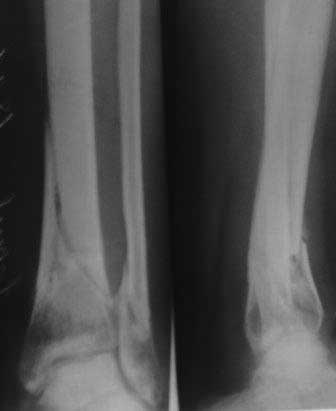

[Ortho] Вялоконсолидирующаяся перелом дистального метадиафиза костей левой голени

Пациентка 32 года, травму получила в результате ДТП, лечилась в гор.б-це №? Москвы с 19.07.по04.08.11г скелетным вытяжением, после наложена гипсовая повязка,(р-снимок 1,2.) после спадения отека гипс переведена в циркулярную, (видимо на другой вид лечения не хватило средств), гипс снят 19.11.11г(снимок-3)

.Жалобы на боли при ходьбе через несколько шагов, увеличение отека в голени и г/стопном суставе, боли ноющего и неприятного характера, хромота, при осмотре отечность голени в с-н/з и г/с суставе, при пальпации умеренная болезненность в н/з голени, подошвенное сгибание в г/с суставе ограничена и болезненна. Работа связана с ходьбой, просить помочь чтобы не потерять работу. Пока в голове только КДО аппаратом Илизарова, уважаемые коллеги  помогите советом! Доступно БИОС, пластины DCP. и прилагается последние р-снимки.